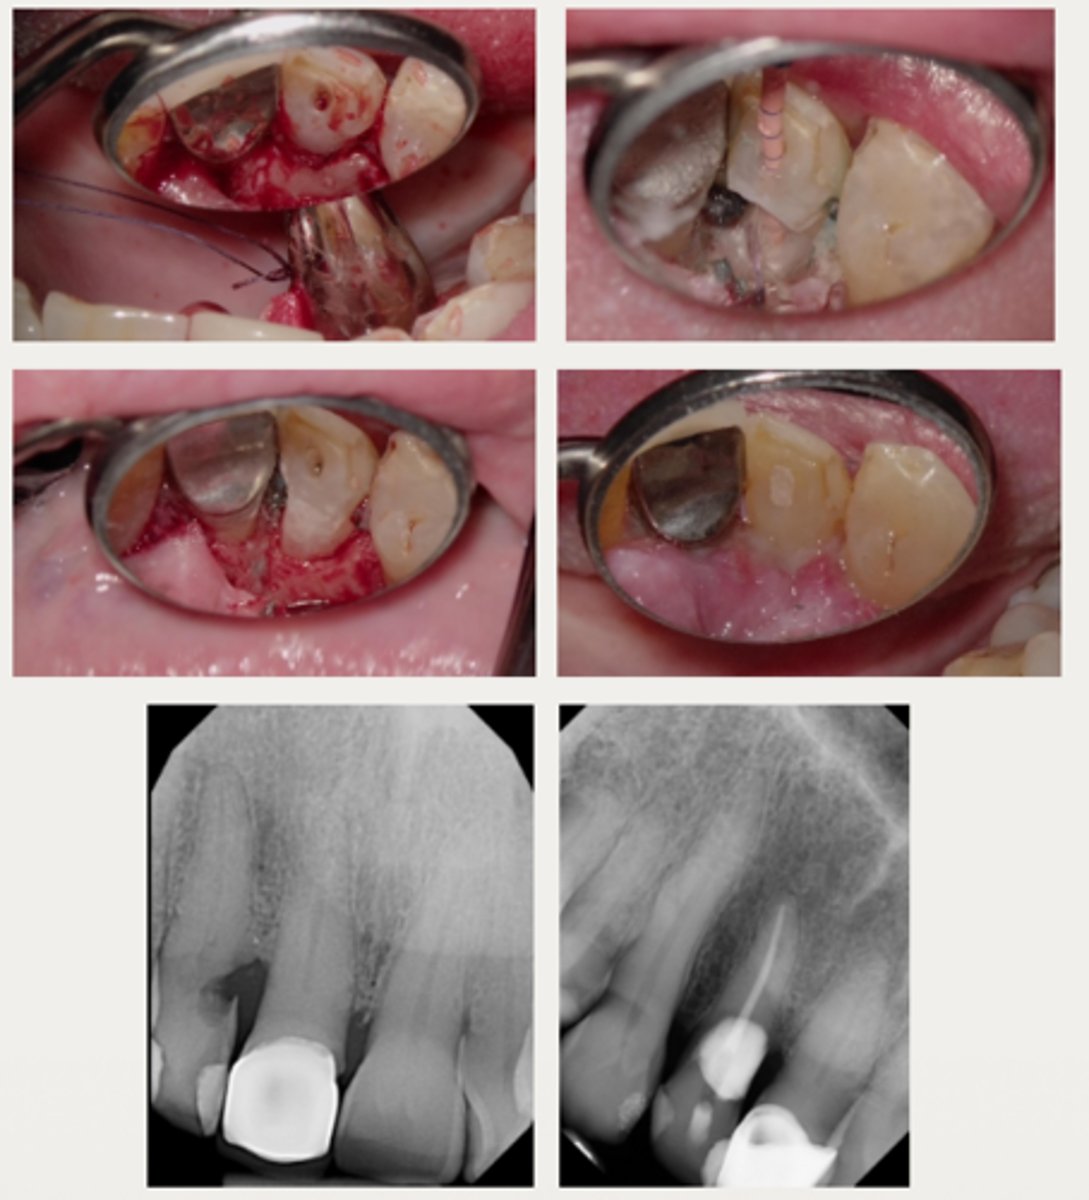

- Monitor the lesion

- Intentional replantation

- Extraction

- External surgical repair only

- External surgical repair with RCT

- Internal repair with RCT

What are six treatments for External Cervical Resorption (ECR)?

External surgical repair only

These are a part of which treatment for External Cervical Resorption (ECR)?

For lesions that are accessible through raising a flap and that are unlikely to have pulpal involvement after removal

- Raise a flap

- Complete debridement of the resorptive lesion

- Tx with 90% trichloroacetic acid (TCA) or 5.25% NaOCl

- Restoration of defect with resin-modified glass ionomer (Geristore) or Biodentine

- Flap closure and suturing

External surgical repair with RCT

For lesions with a large portal of entry where the resorptive defect would be accessible by raising a flap without having to remove excessive marginal bone:

- Same as the external repair only approach

- RCT may be completed before or after the repair, if care is taken to prevent canal blockage when restoring the defect first

Internal repair with RCT

For lesions with a small portal of entry where the resorptive lesion is in close approximation to the chamber/canals

- Root canal therapy is initiated

- Resorptive lesion is debrided through the access cavity using 90% TCA or NaOCl

- Root canal therapy is completed

- Resorptive defect is restored using RMGI, Biodentine, or Bioceramics (ERRM) depending on the level and extent of the perforation